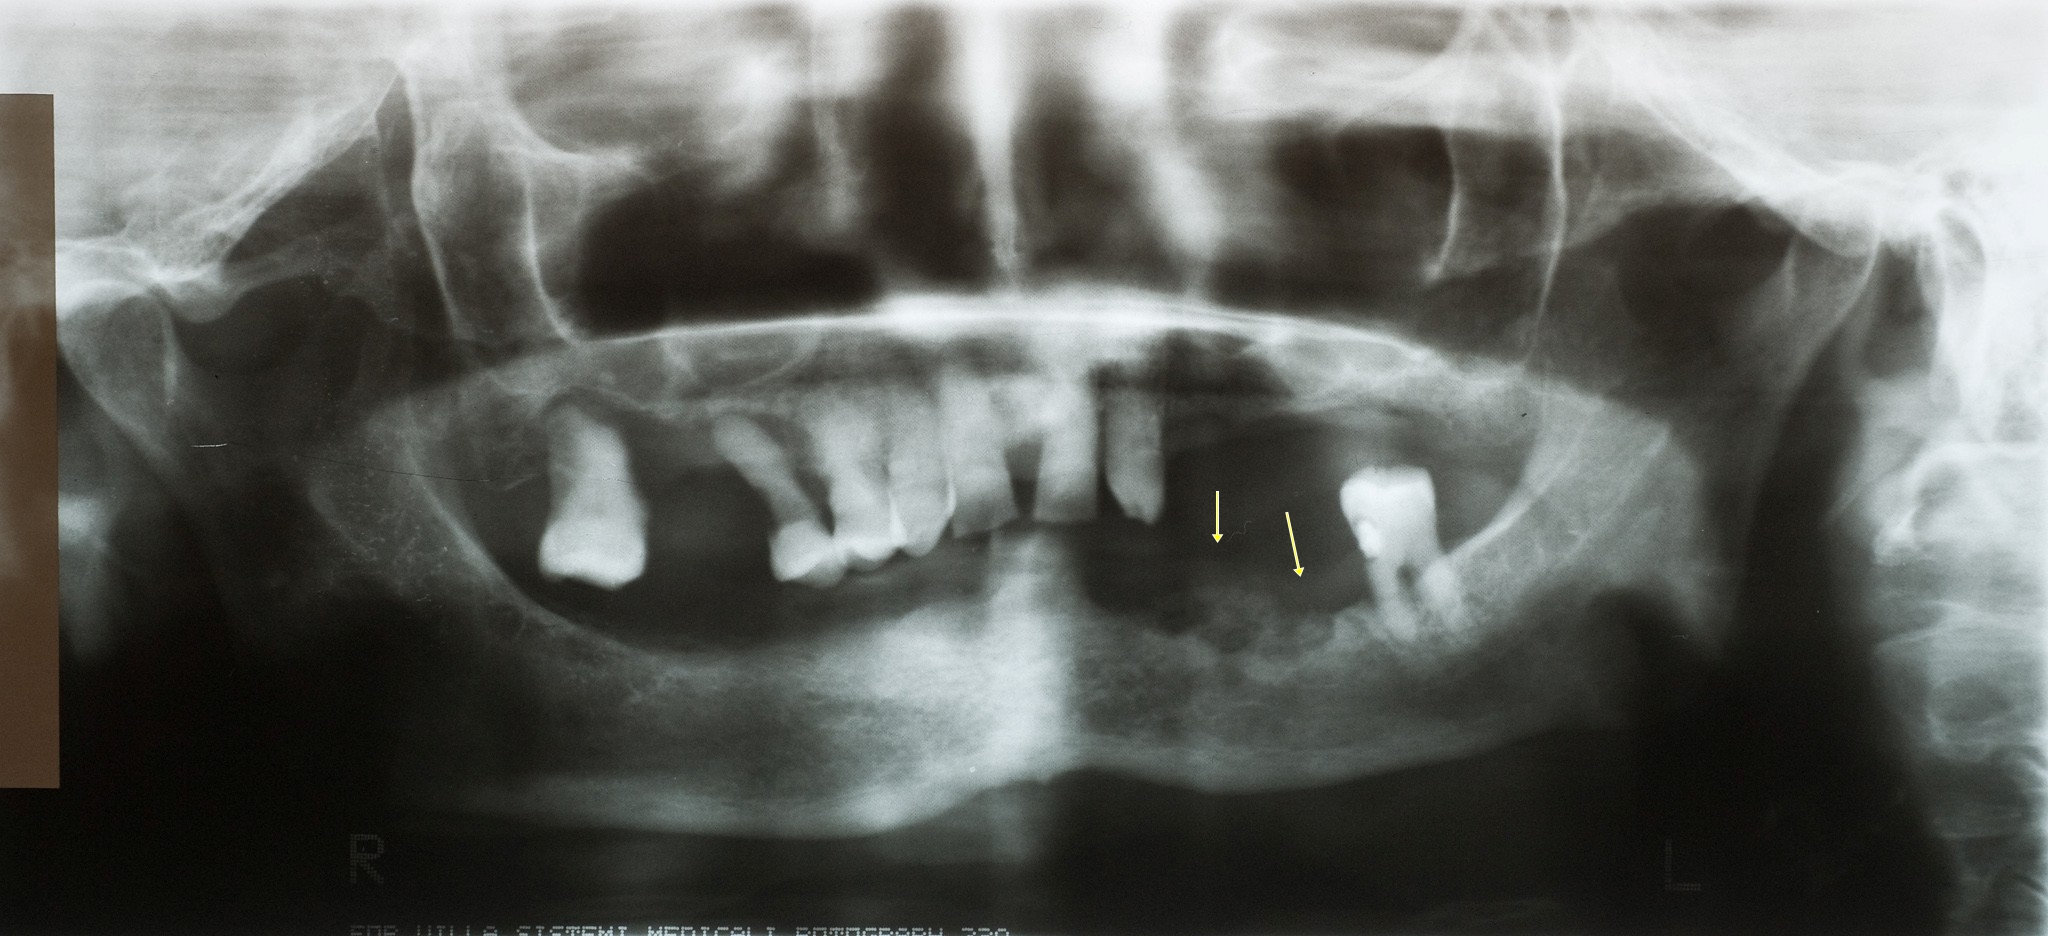

Osteonecrosis de la mandíbula asociada al tratamiento oral con ibandronato